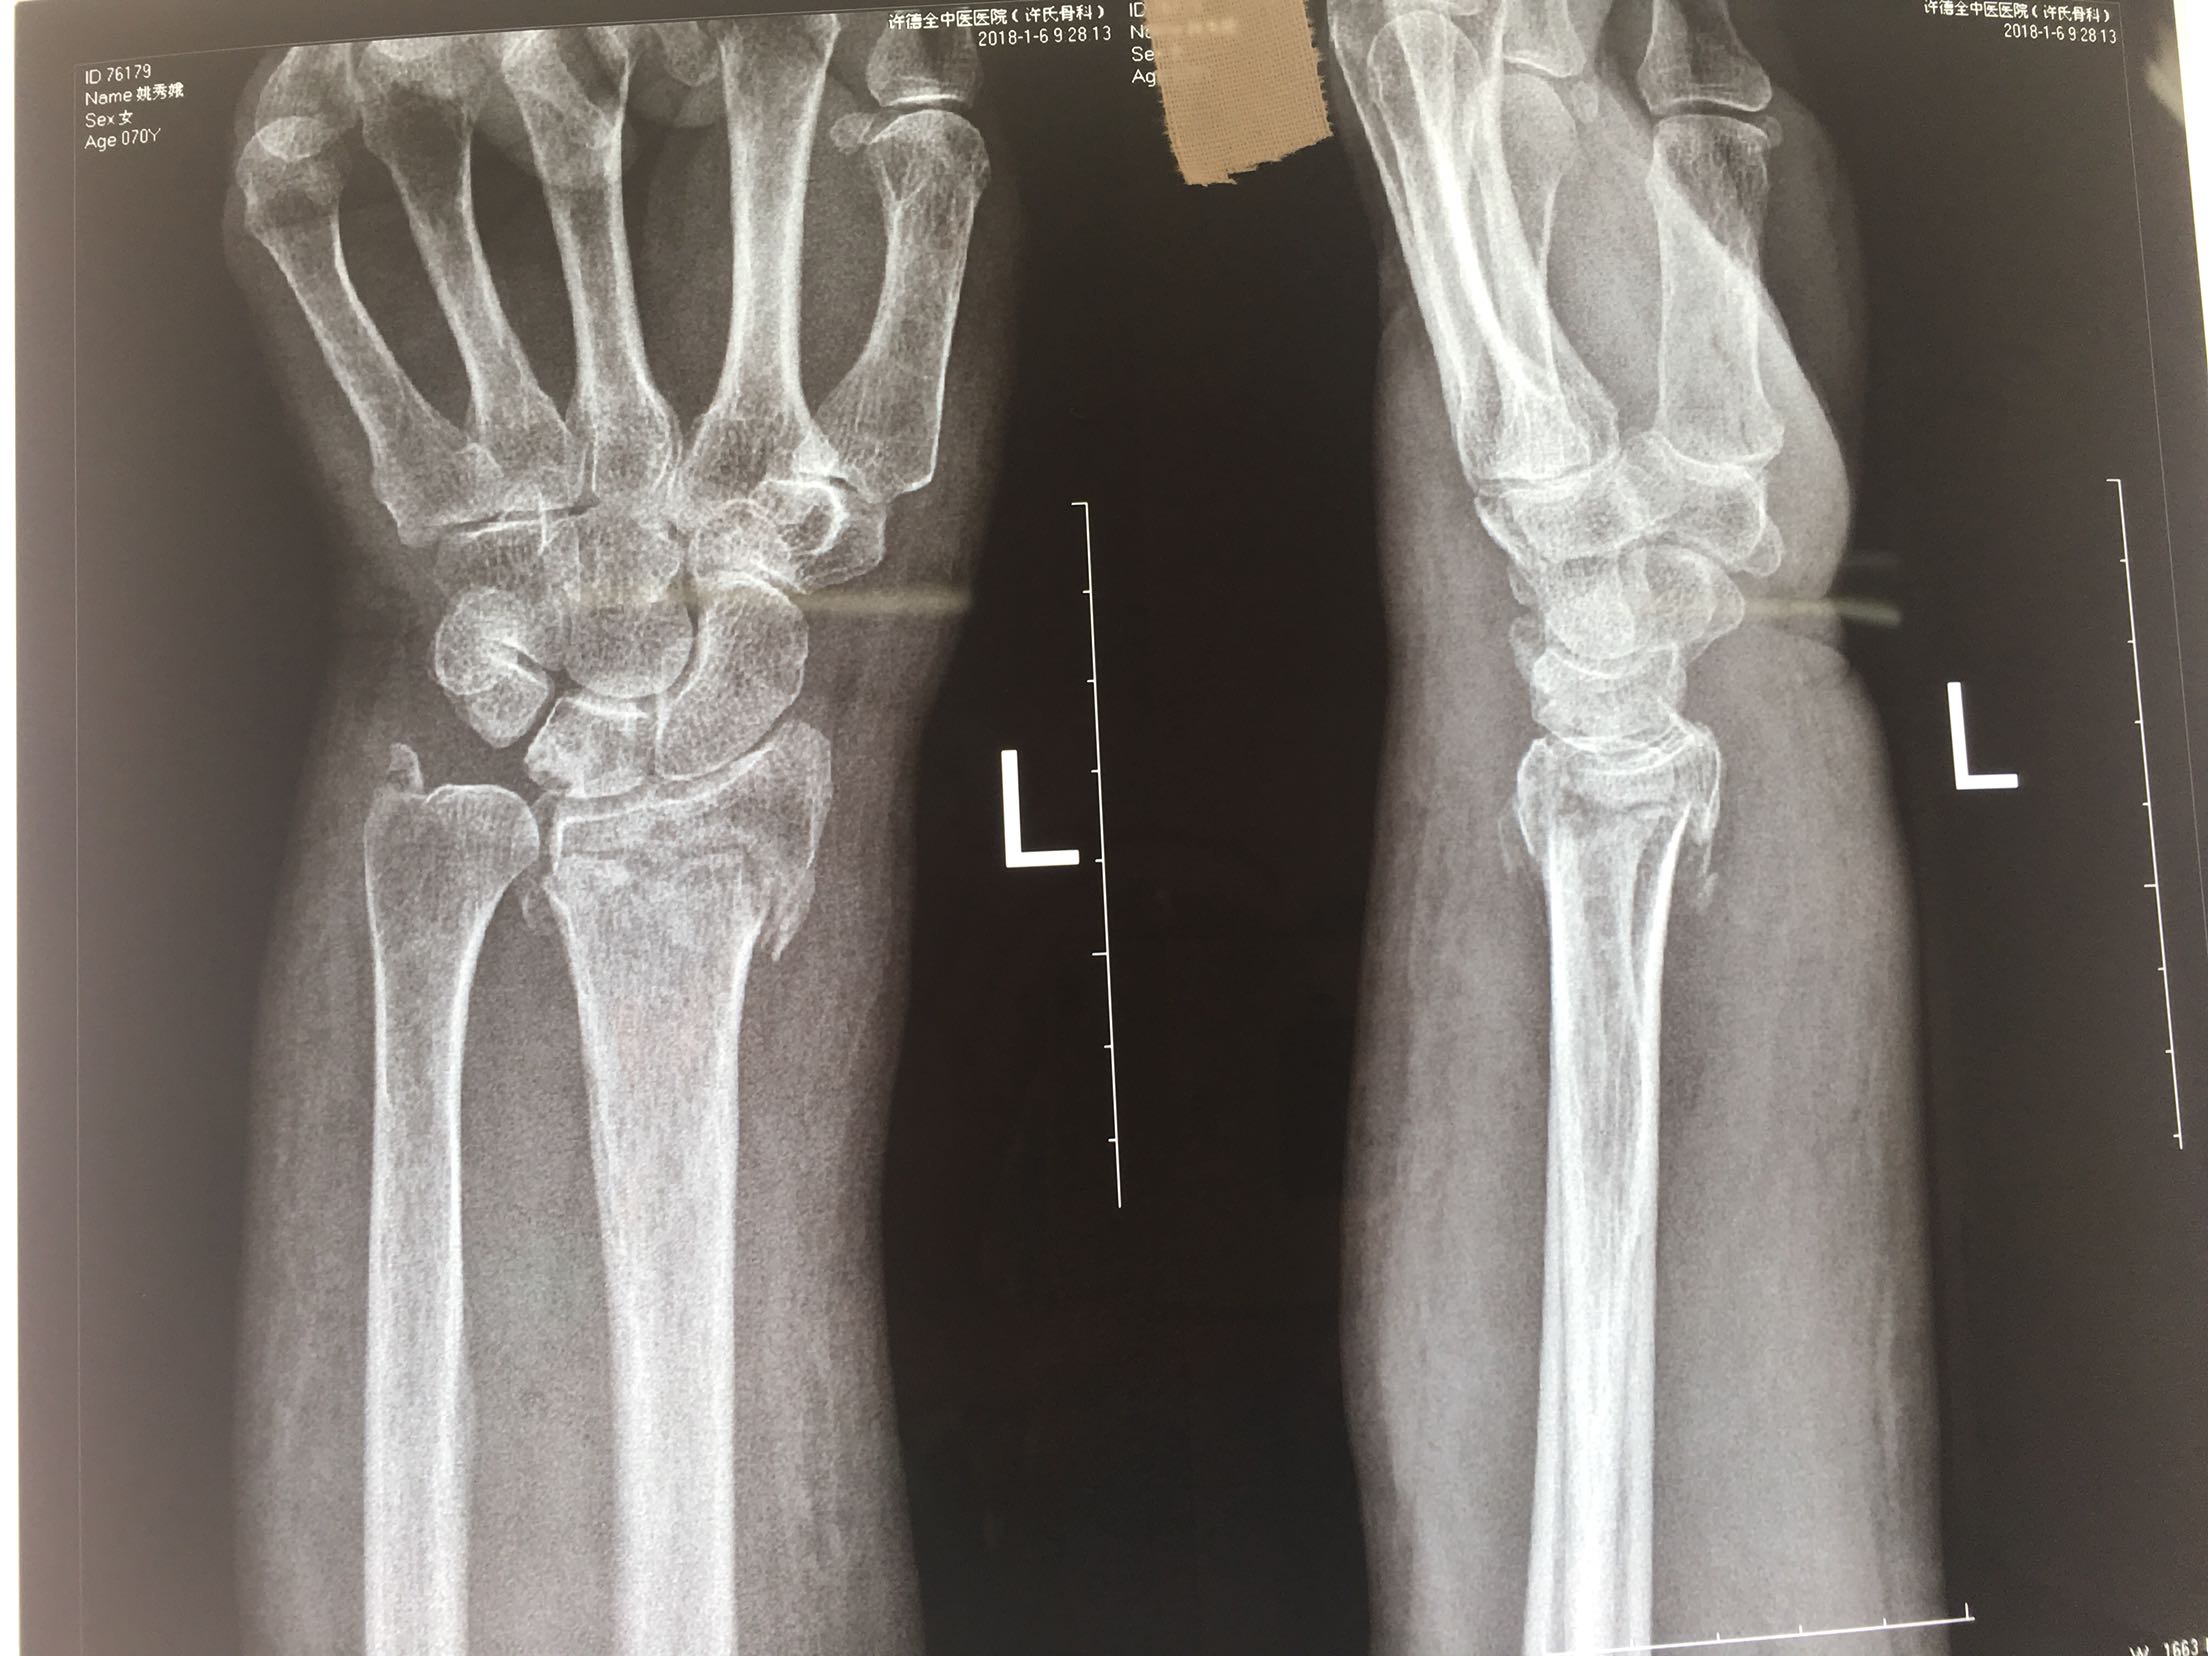

一例保守治疗失败的colles骨折

患者,女性,70岁,摔伤后左腕关节肿痛畸形3天。

左腕部肿胀,局部压痛,皮色皮温正常,畸形,远端感觉血运良好。

在臂丛麻醉下行切复内固定术,术后抗炎,消肿对症处理。